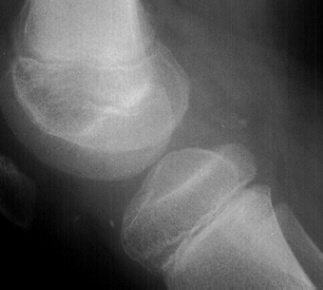

RADIOGRAPHS:

AP, lateral and obliques of the left knee showed an effusion with multiple radiodense bodies that were felt to be intraartictilar . No fractures or dislocations were evident. Comparison views of the right knee were unremarkable.